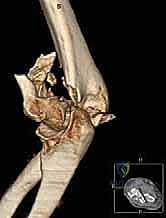

- الأشعة المقطعية ثلاثية الأبعاد (3D CT Scan): يعتبر الدكتور هطيف هذا الفحص إلزامياً في جميع كسور عظم العضد البعيد المفصلية. تتيح الأشعة المقطعية رؤية حجم وشكل وموقع كل شظية عظمية مهما كانت صغيرة، مما يسمح بوضع خطة هندسية دقيقة للجراحة قبل فتح المريض.